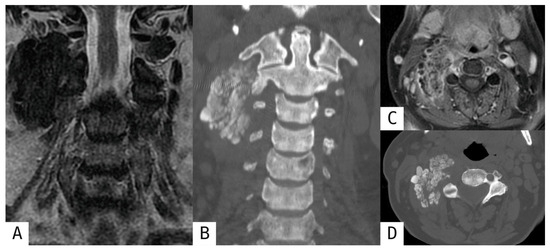

Revisiting Myositis Ossificans: A Comprehensive Stage-by-Stage Imaging Review

by Consolato Gullì, Giuseppe Ferrara, Emanuele Ferravante, Roberto Calbi, Mario Di Diego, Davide Parisi, Daniele Perla, Tommaso Villa and Luigi Natale

Muscles 2026, 5(2), 27; https://doi.org/10.3390/muscles5020027 - 14 Apr 2026

Myositis ossificans (MO) is a benign, self-limiting heterotopic ossification process that typically develops within soft tissues following trauma, although non-traumatic forms have also been described. Despite its benign nature, MO frequently represents a diagnostic challenge, particularly in its early stages when imaging findings [...] Read more.

Myositis ossificans (MO) is a benign, self-limiting heterotopic ossification process that typically develops within soft tissues following trauma, although non-traumatic forms have also been described. Despite its benign nature, MO frequently represents a diagnostic challenge, particularly in its early stages when imaging findings may mimic aggressive soft-tissue tumors, leading to unnecessary biopsies or surgical interventions. This narrative review provides an updated overview of the classification, pathophysiology, and imaging features of myositis ossificans, with a specific focus on the time-dependent evolution of radiologic appearances across different imaging modalities. Radiologic findings are discussed according to disease stage, highlighting key diagnostic clues such as the zonal phenomenon and peripheral maturation pattern. In addition, the main entities included in the differential diagnosis are reviewed, with particular emphasis on imaging features that help distinguish myositis ossificans from soft-tissue sarcomas and other calcified or ossified lesions. Finally, current management strategies and the role of imaging in patient follow-up are summarized. A thorough understanding of the evolving imaging spectrum of myositis ossificans is essential for radiologists and clinicians to achieve an accurate diagnosis, guide appropriate management, and avoid overtreatment. Full article

Show Figures

Figure 1